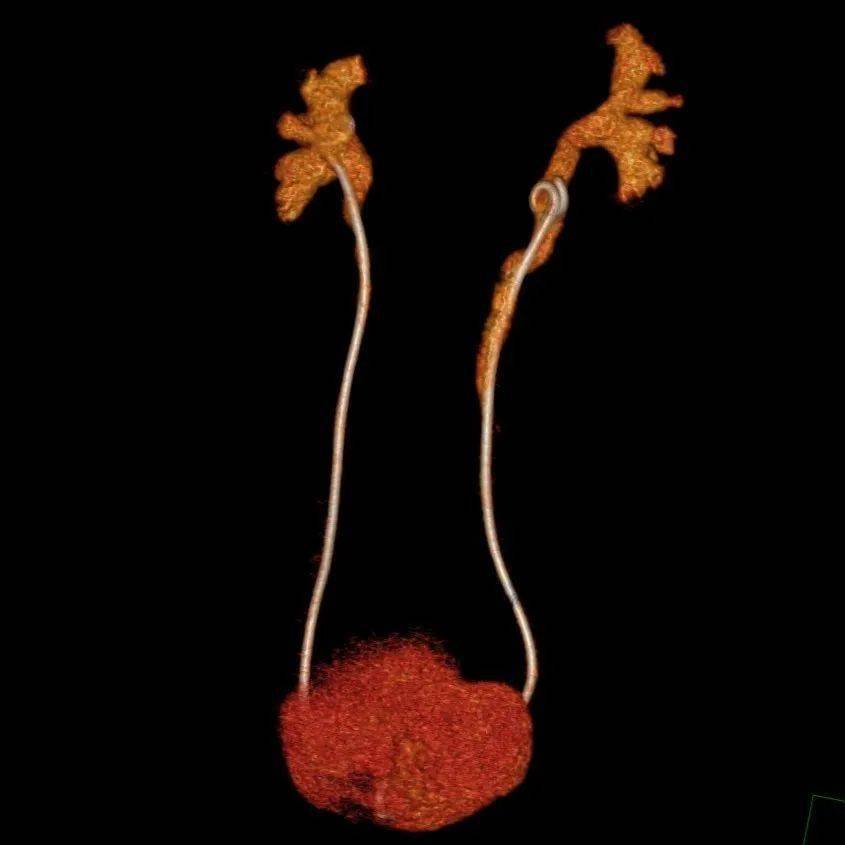

全身各部位血管造影成像,準確了解血管及相關臟器的形態結構,評估血管及臟器功能,準確判斷出血、栓塞、血管瘤、血管畸形、血管狹窄、腫瘤供血等情況。

腹主動脈瘤伴附壁血栓